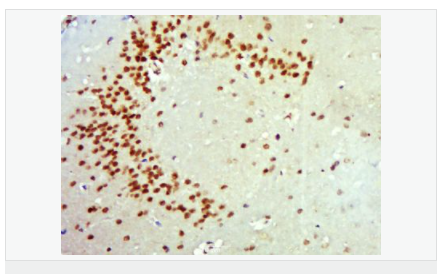

細(xì)胞定位細(xì)胞核 分泌型蛋白

Brain. Highly expressed in hippocampus, amygdala, cerebral cortex and cerebellum. Also expressed in heart, lung, skeletal muscle, testis, prostate and placenta.